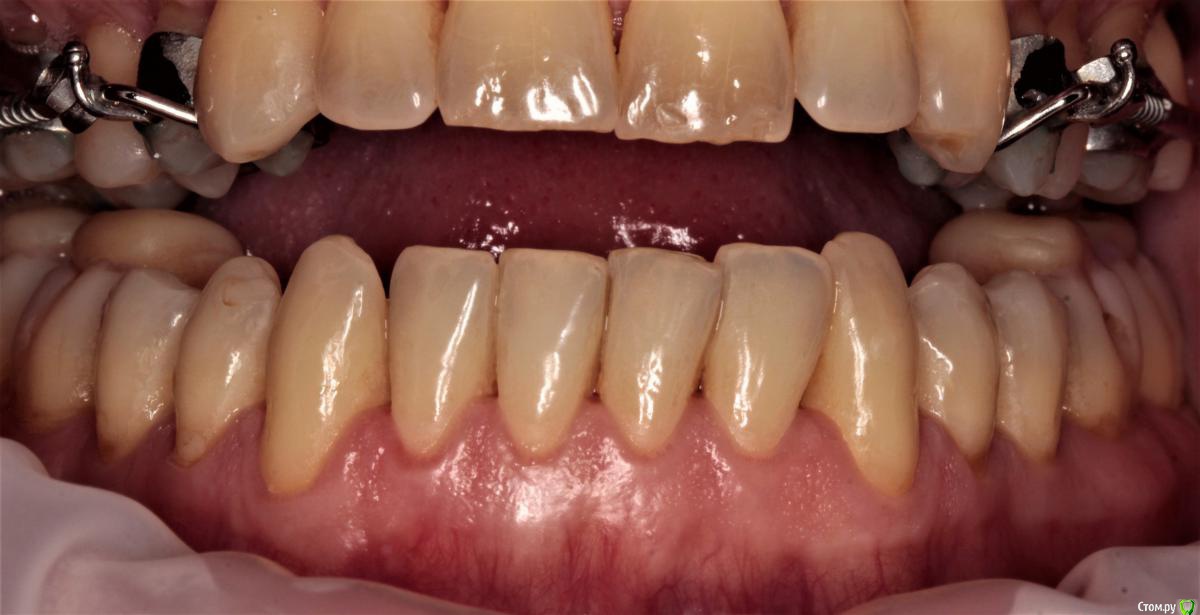

3. сейчас уже пол года мы увеличиваем в длину верхнюю челюсть, что бы наконец устранить причину всего. Потом будем брекетами выпрямлять все оставшееся.

относительно того, что же потом? ортодонт, он же и главный лечащий врач, говорит - типа исправим положение челюстей, выпрямим зубы потом будем думать насчет десен и сосочков - хиругрия и/или ортопедия.

так же мы понимаем, что сосочки это не только эстетика, но и важный функционал всей системы. И без них жить нельзя. При этом, технологии их восстановления, после некроза, не существует.

Я вижу вариант, полного протезирования всех зубов нижней челюсти, максимально закрыв отсутствующие сосочки. Если я понимаю правильно, то зачем тогда нам выпрямлять зубы нижней челюсти, травмируя кость и провоцируя дальнейшие рецессии? Не правильнее ли с помощью протезирования сразу придать им нужную форму и положение? Тем более раскрыв скученный перед у нас там дыры такие же как в боковых отделах будут...

сосочки утеряны вследствие пародонтита. Восстановить их почти нереально. Только ортопедически, изменив форму зубов.